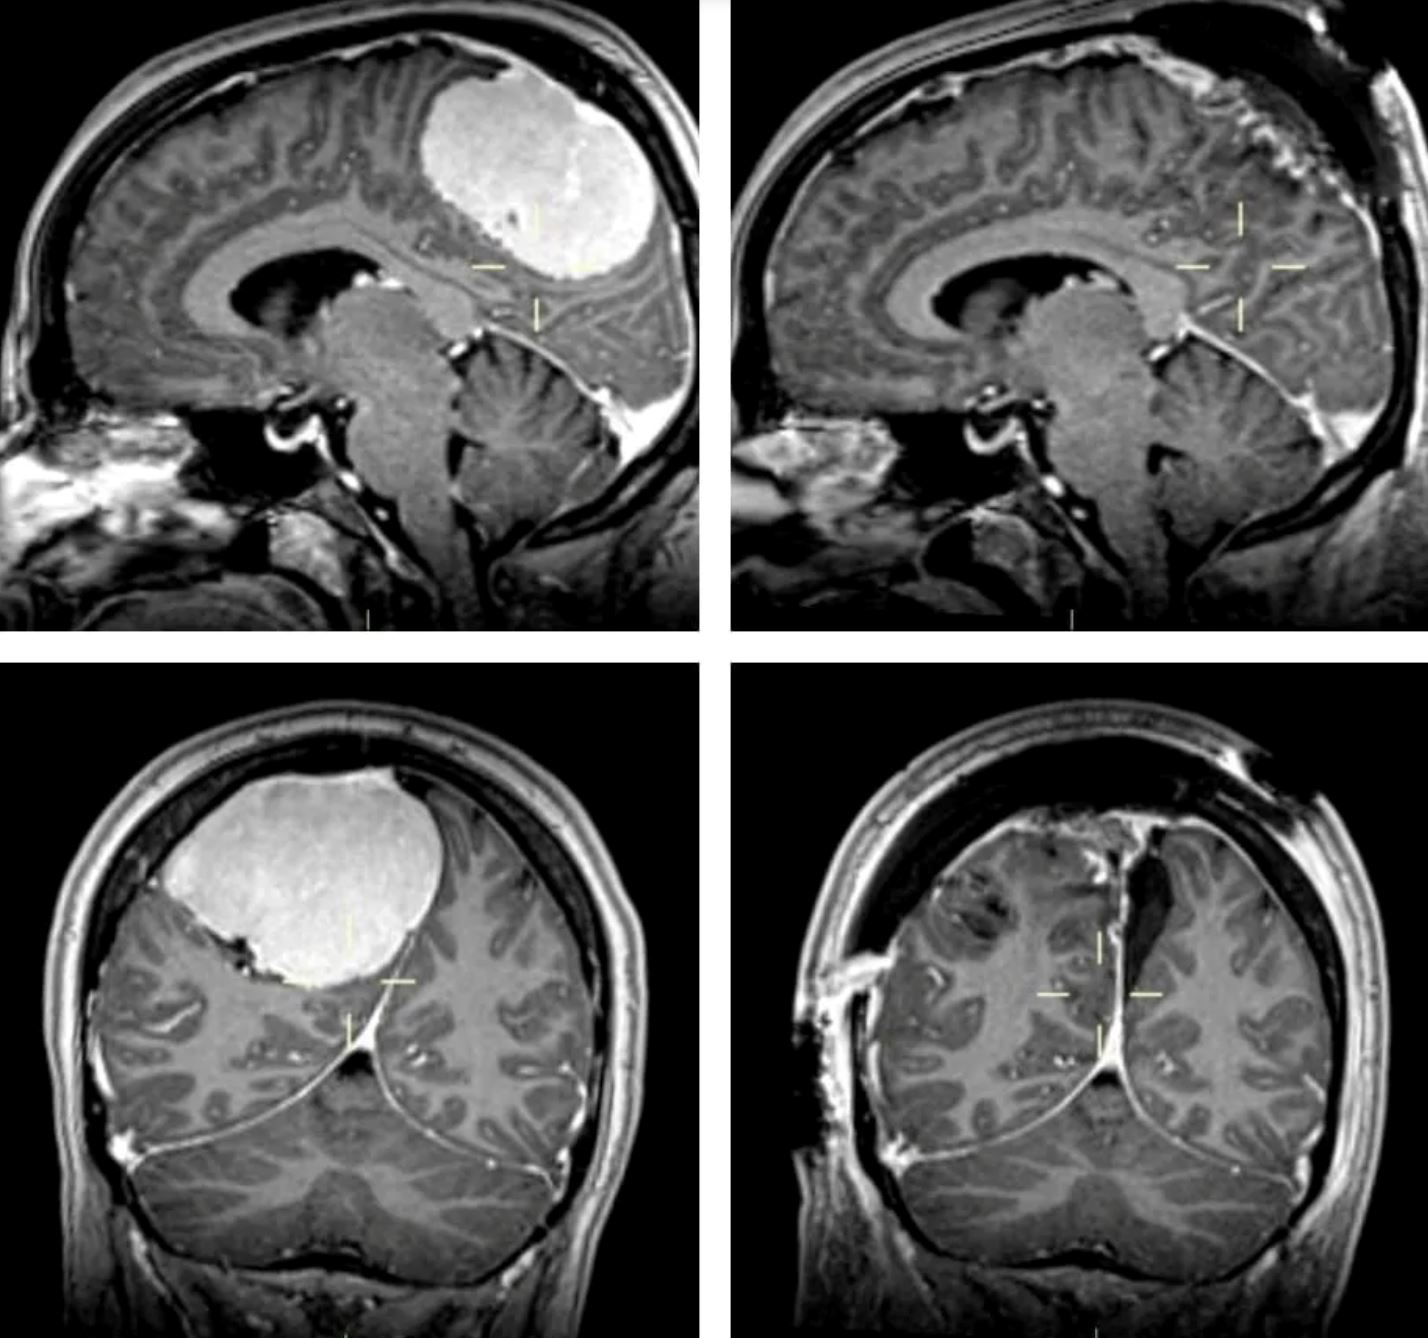

Hasil imbasan CT dan MRI mendedahkan bahawa dia mempunyai tumor otak yang besar pada lebar empat inci, yang terbesar yang pernah dilihat oleh pakar bedah pembedahan itu.

Menurut pakar, tumor itu menolak otak Lisa ke hadapan kepalanya sehingga menyebabkan tekanan dan pening.